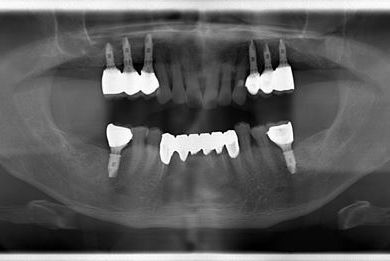

インプラントの症例写真 IMPLANT

骨再生スピードインプラント治療

| 治療内容 | インプラント8本(サイナスリフト、ソケットリフト、GBR)、メタルボンドセラミック8本 | ||||||||||||||||||||||||||||||||

| 治療期間 | 1年5ヶ月 |